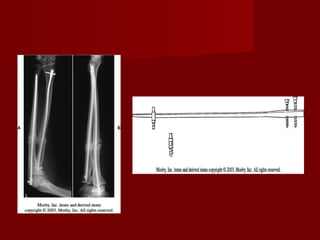

Fracturas de la diafisis del

radio y cubito

   Las fracturas de ambo

huesos del antebrazo

producirá una grave

secuela funcional si no

se trata adecuadamente.

   La pérdida funcional

puede aparecer incluso

tras      la   adecuada

consolidación    de   la

fractura.

Para evitar las limitacion

funcional debe

mantenerse

correctamente las

relaciones:

-   Radio humeral.

-   Radio cubital proximal.

-   Humero cubital.

-   Radiocarpiana.

-   Radio cubital distal.

-   Espacio interoseo

Los metodos de fijación

pueden ser:

- intramedulares.

- Fijación con placas

compresivas o no.

 Si se colocan placas en

radio: en el tercio distal

puede ser anterior y en

el tercio proximal como

esta indicado. En el

cubito es independiente.

Sage

True-flex

ForeSight